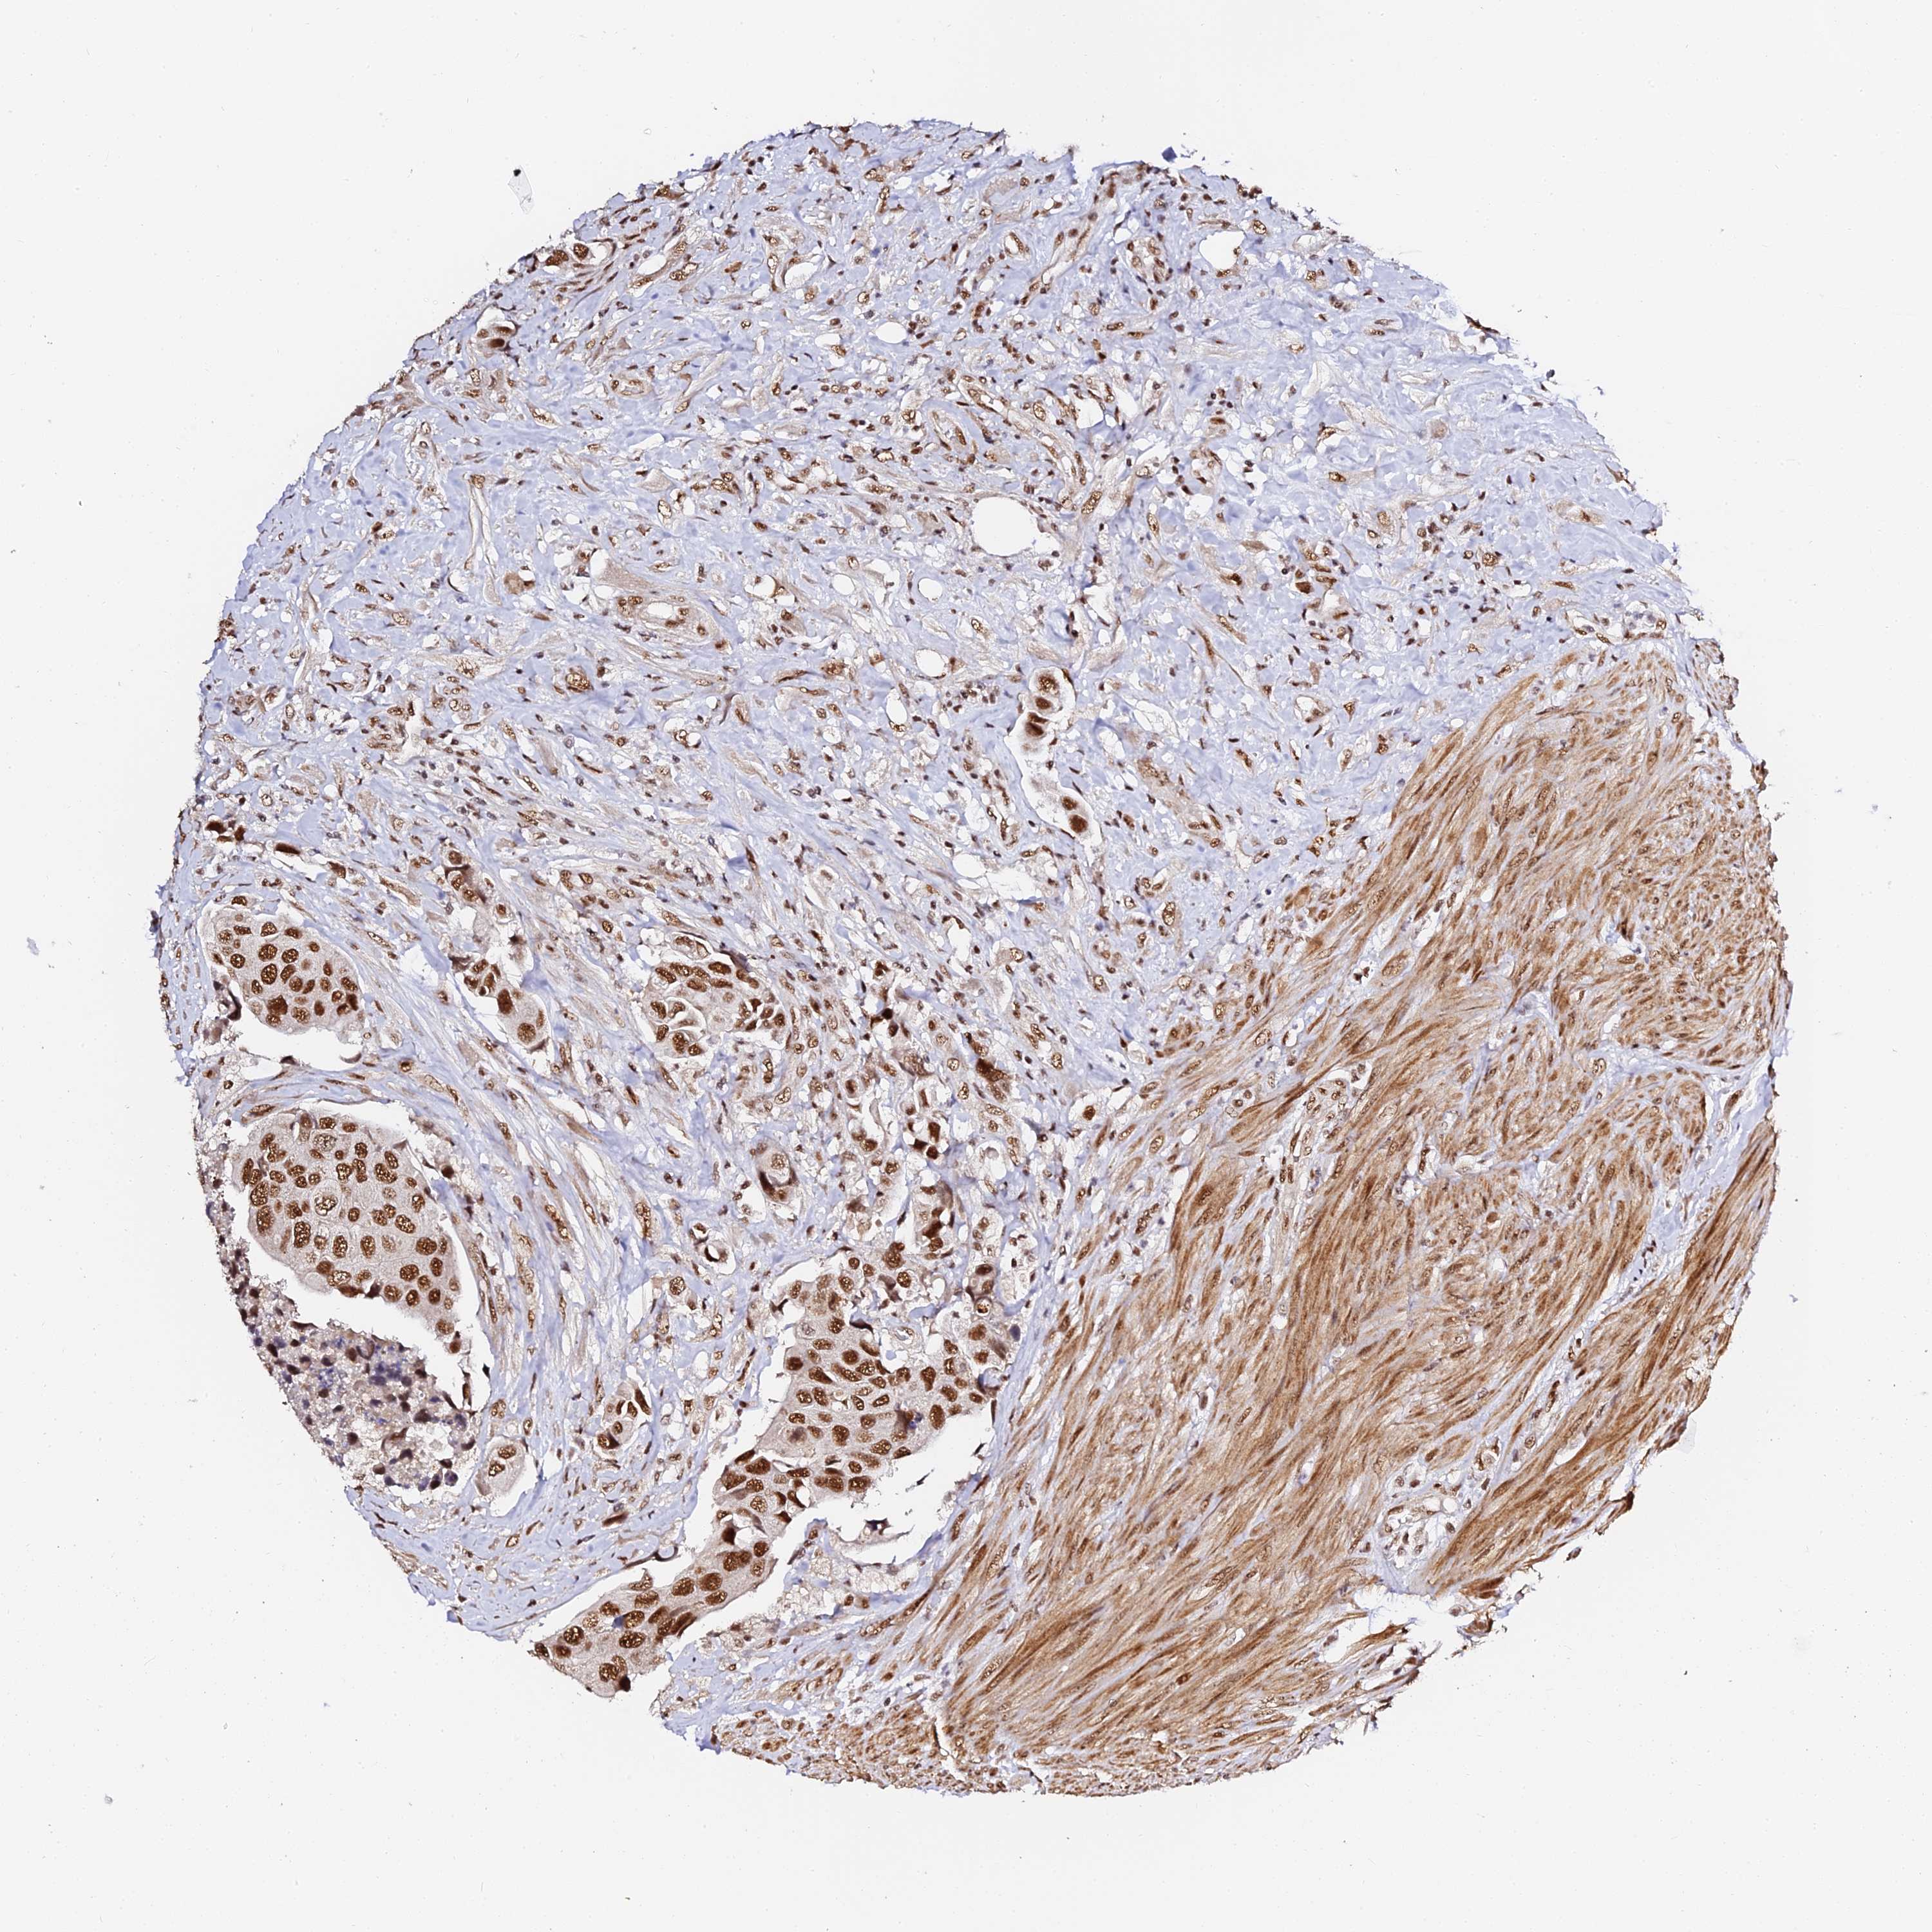

UROTHELIAL CANCER - Protein expressioni

A mouse-over function shows sample information and annotation data. Click on an image to view it in a full screen mode. Samples can be filtered based on level of antibody staining by selecting one or several of the following categories: high, medium, low and not detected. The assay and annotation is described here.

Note that samples used for immunohistochemistry by the Human Protein Atlas do not correspond to samples in the TCGA dataset.

Antibody stainingi

Antibody staining in the annotated cell types in the current human tissue is reported as not detected, low, medium, or high, based on conventional immunohistochemistry profiling in selected tissues. This score is based on the combination of the staining intensity and fraction of stained cells.

Each image is clickable and will lead to virtual microscopy that enables deeper exploration of all samples and also displays staining intensity scores, fraction scores and subcellular localization as well as patient and tissue information for each sample.

Antibody HPA039057

Staining

High

Medium

Low

Not detected

Intensity

Strong

Moderate

Weak

Negative

Quantity

>75%

75%-25%

<25%

None

Location

Nuclear

Cytoplasmic/membranous

Cytoplasmic/membranous,nuclear

Urothelial carcinoma, High grade

Urothelial carcinoma, Low grade

Urothelial carcinoma, NOS